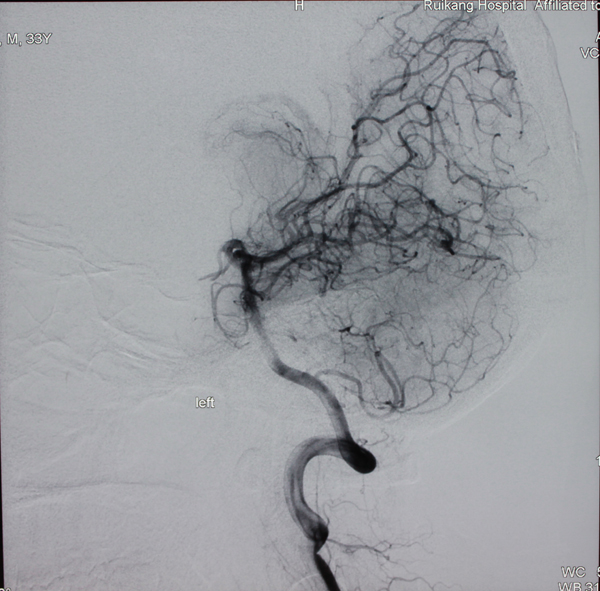

对于动静脉畸形的治疗,主治医师李亚平介绍,有三种方式:开颅切除手术、介入治疗和放射治疗。开颅手术效果最彻底,能够将动脉畸形根除,是治疗动静脉畸形的最理想方式,但对于位于功能区的畸形和不适宜手术治疗的患者可采取放射治疗或介入治疗,同样能够起到良好的效果。“神经外科医生会根据动静脉畸形在大脑中所处的位置及病人的发病情况来选择最适合的治疗方案。”

手术后

清除脑动静脉畸形后李明开心留影